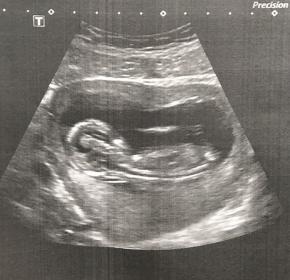

Any guesses with the Ramzi theory? Attachment 34815

No nub, appears to be we are looking at babiy's back x